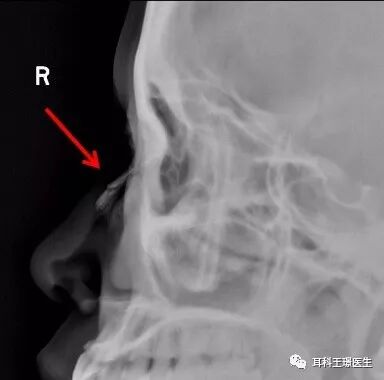

鼻骨骨折 鼻骨骨折とは、ケガや転倒などで鼻の骨が折れた状態です。 「鼻の骨が折れたかな? ? 」と不安でしたら病院を受診してCTで骨折していないか調べてもらうのがいいと思います。 折れている場合は、見た目で曲がっていることが気になるよう Waters法や鼻骨側面撮影法などの単純X線検査( 図1 ),軸位CT( 図2 ),さらに触診によってほぼ正確に診断することが可能である 1) 。 周囲骨(軟骨)構造との関係で,鼻骨骨折は,①鼻骨陥凹骨折,②openbook型,③鼻骨鼻中隔複雑骨折,の3つのタイプに